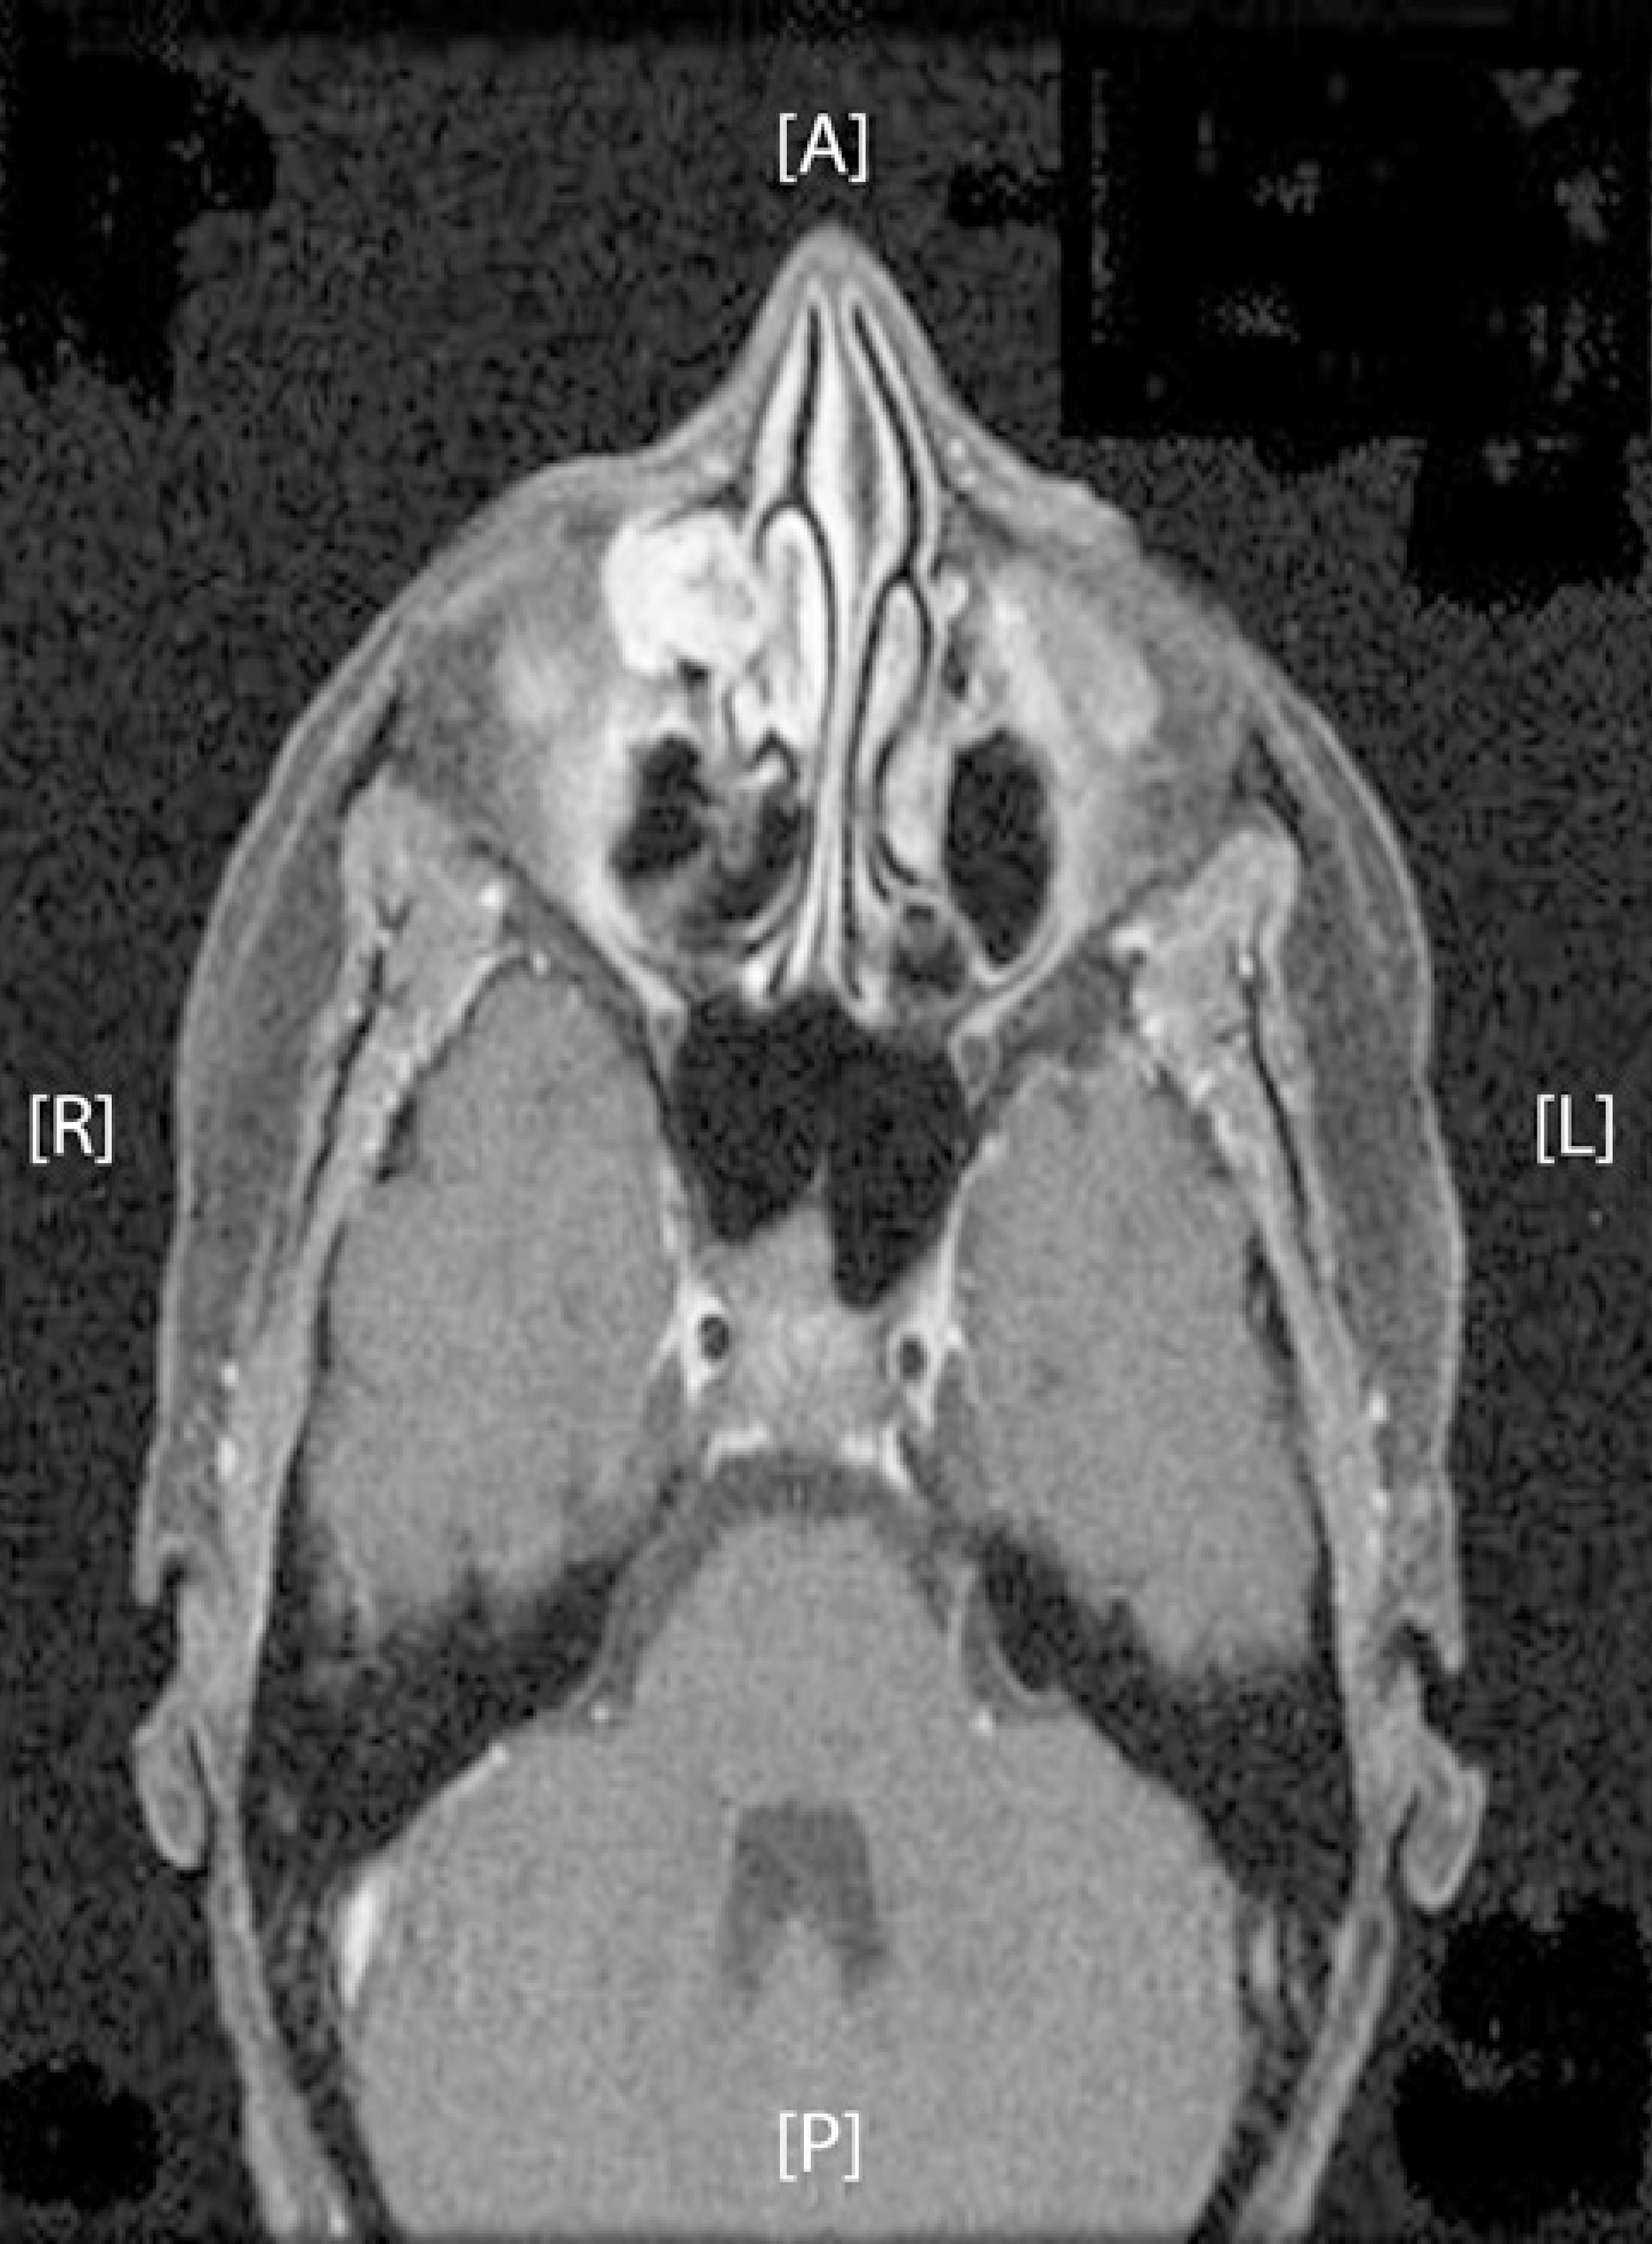

In August 2013, the patient was re-attended complaining of pain in the right canthus and mucosanguineous secretions from the lacrimal punctum in response to pressure. A new DCG was performed demonstrating a filling defect in the sac without passage of contrast into the distal duct. Orbital magnetic resonance imaging identified a solid-cystic lesion measuring 17 × 17 × 13 mm in the right lacrimal sac seen extending towards the orbit and infiltrating the extraconal fatty tissue (Figure 1). Right dacryocystectomy was performed following observation of a gelatinous mass infiltrating the lacrimal sac and eroding the surrounding bony structures. Pathologic examination demonstrated ACC with a predominantly cribriform pattern infiltrating the muscle and bone tissue with additional perineural infiltration (Figure 2). In the extension study, no signs of tumor spread were evident. Further intervention with right lateral rhinotomy located the mass to the canthal area. The tumor planes were dissected and an osteotomy was performed from the canthal ligament to the orbital floor. The orbital floor was reconstructed before tension-free closure and approximation of the rhinotomy flap. Pathological examination of the dissected tissues confirmed the existence of ACC. Following surgery, the patient had a favorable clinical course. A multidisciplinary approach was established, and the patient received 33 sessions of radiotherapy with no signs of recurrence observed after a follow-up for 2 years.

Figure 1 Solid-cystic lesion occupying the right lacrimal sac region consistent with a neoplastic process.